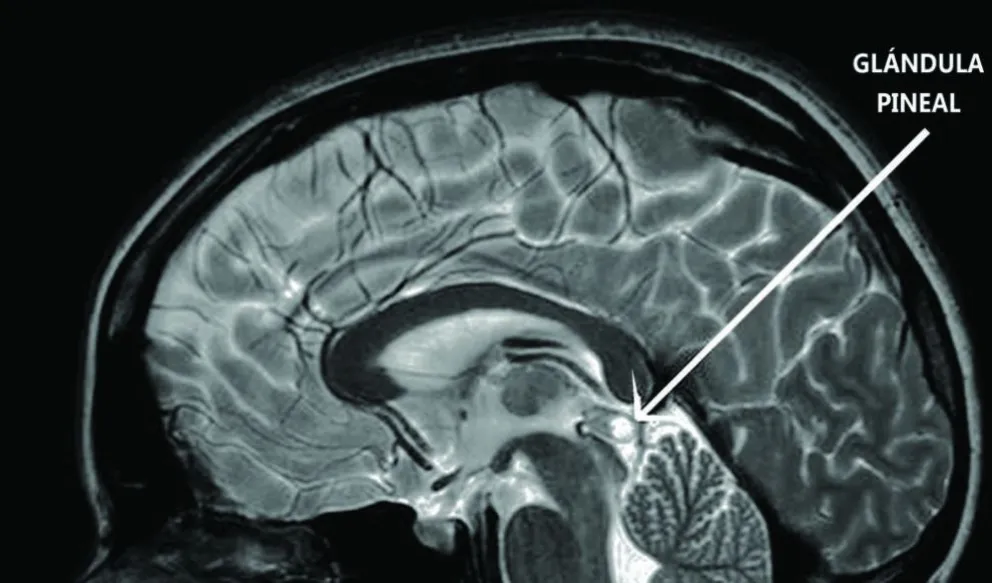

En un artículo anterior, te comenté sobre la propuesta de la “Teoría Cuántica de la Conciencia” donde se dice que el alma se localiza en los microtúbulos a lo largo de todo el cerebro a escala cuántica, pero existe otra teoría que dice que el alma reside en una sola glándula de nuestro cerebro, y a pesar de su pequeño tamaño, el cuerpo parece darle mucha importancia. Esta es la glándula pineal, también llamada cuerpo Pineal, Conario o Epífisis Cerebral. Esta pequeña glándula pertenece a las llamadas endócrina, que son aquellas que poseen la característica de secretar hormonas. En este caso lo que produce es melatonina, que es más conocida por ser la responsable de controlar el ciclo del sueño. Esta posee forma de un pequeño fruto o piña de pino. Esa es la razón por la que recibe el nombre de Pineal con un tamaño entre 5 y 8 mm, algo realmente pequeño y, sin embargo, recibe un enorme flujo de sangre equivalente al que reciben nuestros riñones, razón suficiente para entender su gran importancia, en el funcionamiento del cuerpo.

Algo que ha llamado la atención de los estudiosos es la posición donde se localiza la glándula pineal, pues se encuentra justo en medio del cerebro, además de alinearse con el centro de nuestra frente, por ello se le considera como el Tercer ojo o el Sexto Chacra.